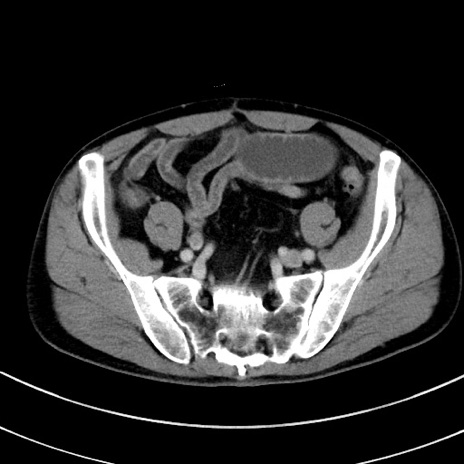

症例8(横断像)

【症例】 60歳代男性

【主訴】 黒色吐物

【現病歴】 4日前から嘔気自覚、2日前の朝食後にも嘔気あり、自分で手で嘔吐反射起こし嘔吐したところ血が混ざっていたため受診。

【既往歴】 5年前汎発性腹膜炎を伴う急性虫垂炎で手術、高血圧、前立腺肥大症、高脂血症

【身体所見】 腹部正中に手術癩痕あり 腹部平坦・軟圧痛なし膨満感あり

【データ】WBC 8400、CRP 4.54